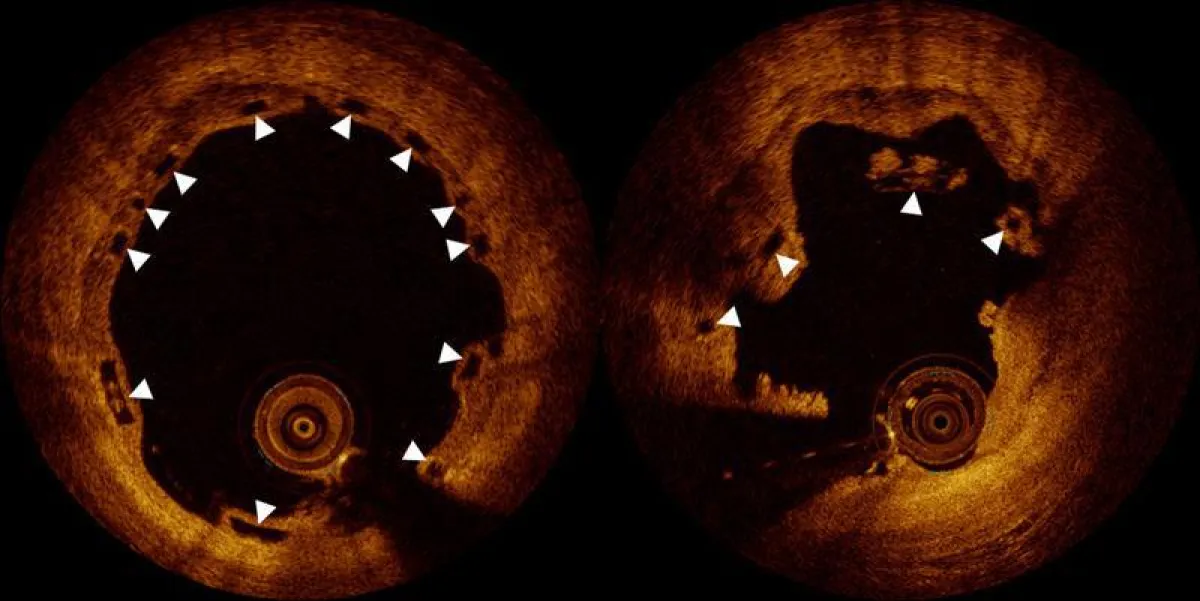

It was initially unclear why complications occurred. Now, researchers at Bern University Hospital have discovered the cause, under the leadership of cardiologist Prof. Dr. Lorenz Räber. The cardiologists at Bern University Hospital examined 36 patients, in cooperation with universities in Europe and Asia, who suffered from late bio-stent blockages beyond one year after implantation. The cause was only detectable by high-resolution imaging called optical coherence tomography. This technology provides nearly microsopic images from the inside of the blocked stent.

«The findings were surprising», says Lorenz Räber. «Although the stents were implanted correctly, we realized that stent fragments had penetrated the inside of the vessel.» Actually, the stent is doing what it was conceived for: It is dissolving into individual fragments. «However, if these fragments have not yet completely grown into the vessel wall, they can get into the bloodstream, potentially leading to dangerous blood clot formation, and subsequently to a heart attack.»